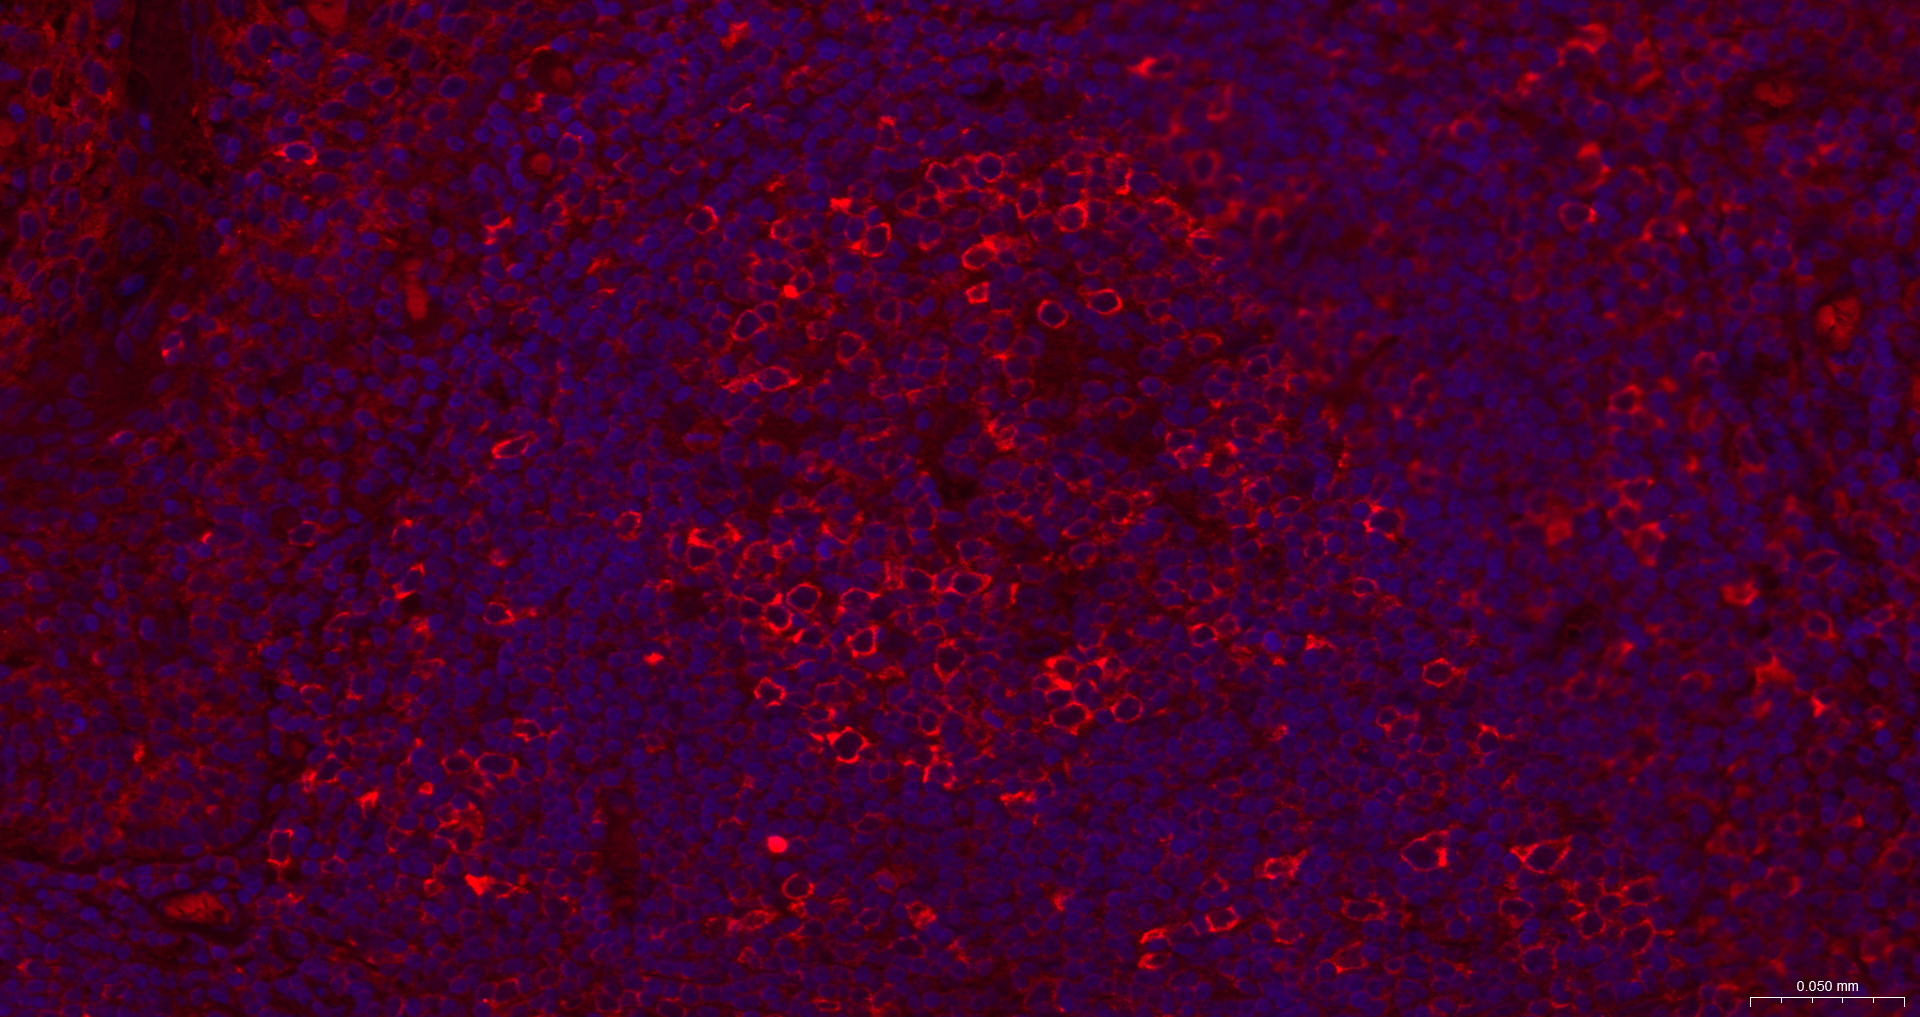

IF(ICC) IFICC1:50-200